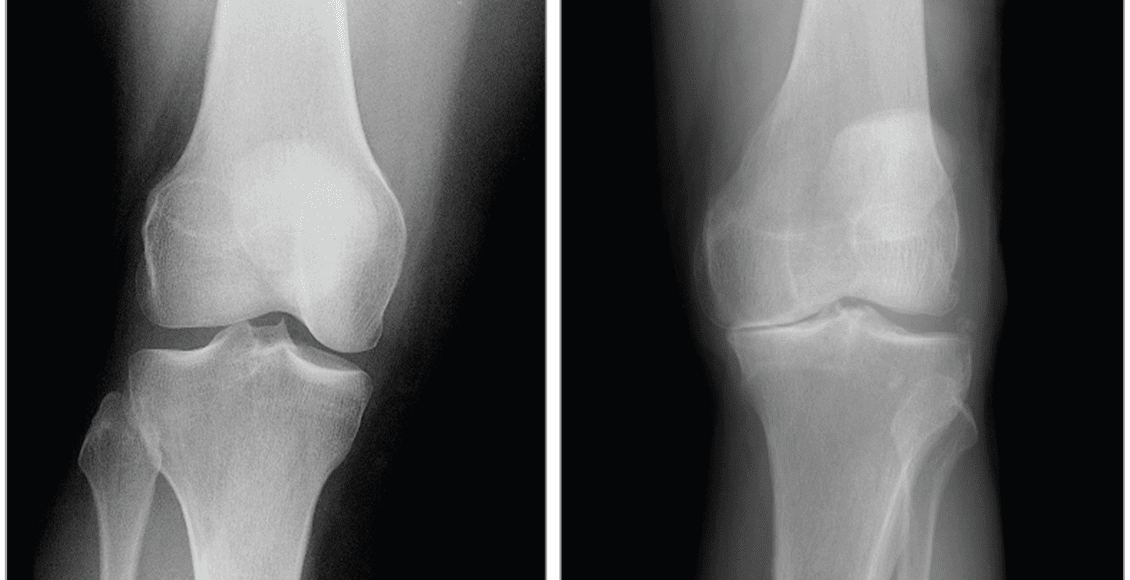

- X-rays. These imaging diagnostic tests produce images of compact structures, such as bones. They can help distinguish among various forms of arthritis. X-rays for knee arthritis may demonstrate a portion of the joint distance, changes in the bone as well as the formation of bone spurs, known as osteophytes.